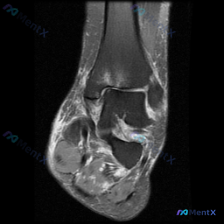

最近碰到一个有意思的病例,核心矛盾是「主诉考虑软骨异常,但影像学没看到明确病变」,整理出来和大家分享一下思路。 病例基本信息 核心问题:患者主诉提示膝关节存在软骨异常,仅提供单张膝关节MRI-T1序列矢状位影像,已完成影像读片分析。 影像读片结果 1. 骨性结构:股骨远端、胫骨近端、髌骨骨皮质完整,...